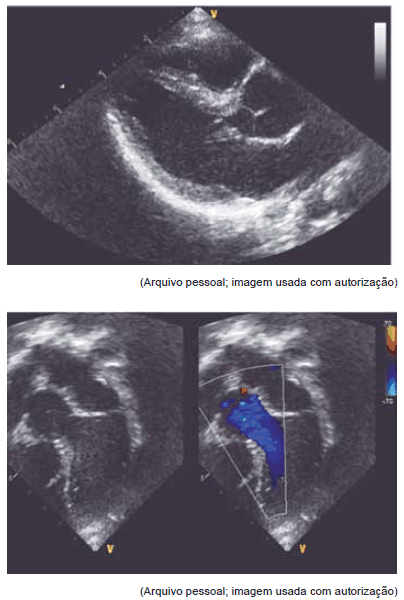

Estas imagens de ecocardiograma dizem respeito a paciente com síndrome

Provas